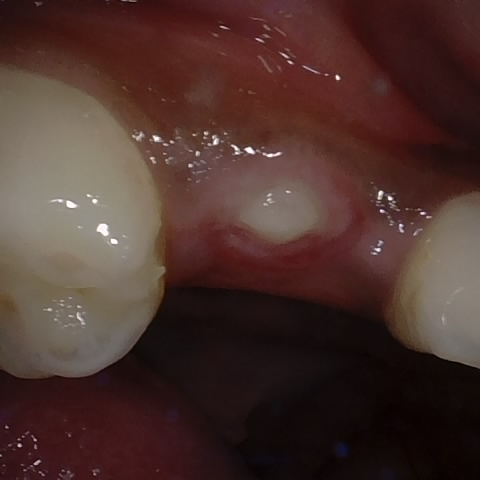

Annotated as "Good"